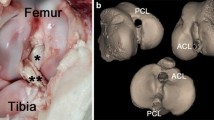

The kinematics of an ACL-substituting implant (ASCR) was compared to that of the same tibial articular surface without a post but with an intact ACL (BCR). This allowed for a direct comparison of the kinematic function of the ACL-substituting post, and the modelled ACL, for a given femoral and tibial articular surface design (identical for all tested implants). The ACL-substituting design tested in this study included an anterior tibial post that substitutes for the native ACL by interacting with the anterior portion of the femoral intercondylar notch. This concept of replacing the native ACL function is analogous to the concept of replacing PCL function in posterior stabilized (PS) implants using a post–cam interaction. The ACL-substituting post is also designed to accommodate the intact PCL (Fig. 2).

The abnormal posterior femoral location in CR implants is largely due to the missing ACL, which is under tension in extension and holds the femur anteriorly on the tibia (Fig. 6). Following this posterior shift, the force imbalance within the joint causes paradoxical anterior sliding of the femur in early flexion. As explained by Blaha, the line of action of the body weight in early flexion lies behind the knee joint. This is balanced by quadriceps activation, and the absence of the ACL and slack state of the PCL in early flexion causes anterior femoral sliding [4]. To reduce such paradoxical anterior sliding, contemporary TKA implants often utilize increased anterior tibial lips, which also cause the femur to sit posteriorly on the tibia in extension. With increased flexion, a reduced tibiofemoral constraint allows additional laxity, and paradoxical anterior sliding occurs until the PCL is adequately tensioned in mid-flexion to guide femoral posterior rollback.

In contemporary CR TKA, the ACL is resected and its function is lost, which alters native knee kinematics following TKA surgery [23, 35, 43]. ACL retention is one way to overcome these kinematic abnormalities but presents several challenges as previously discussed. Therefore, the goal of this study was to determine whether the kinematic abnormalities of CR implants could be improved by substituting for the resected ACL. This is achieved by the interaction of a tibial post with the intercondylar notch of the femoral component at low flexion angles to provide anteroposterior stability similar to that provided by the ACL in the native knee (Fig. 6), [33]. Further, the ACL-substituting tibial post is intended to work in conjunction with the native PCL. At higher flexion angles, the ACL post is designed to disengage from the femoral component and allow motion/stability to be governed by the native PCL.